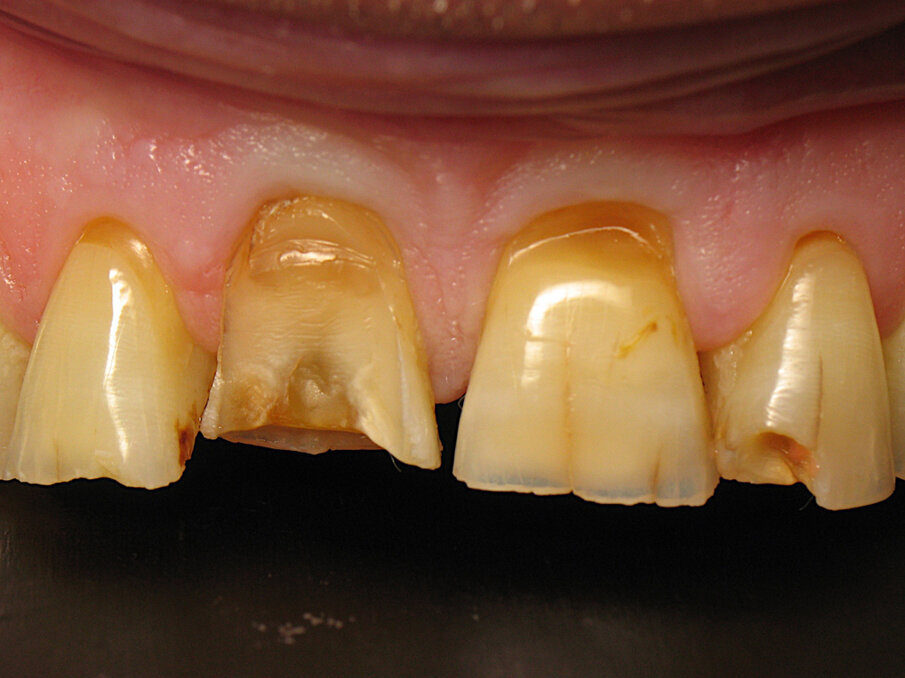

Taken a week earlier, Figures 8 and 9 show the dental preparation and the placement of the first gingival retraction cord. The form of preparation left sufficient margin for the technician to design the crowns. The gingival retraction cord was placed during the preparation phase to avoid injury of the cervical gingiva and to move it apically. It was thus possible to achieve juxta-gingival limits respecting the dental anatomy and periodontal health. It is interesting to note that the tooth shade is not homogeneous between the teeth and within the tooth itself. We will go back in time to understand this phenomenon.

Taken 1 hour earlier, Figure 10 shows a real patchwork of tooth shades. There was translucency of the incisal edge, cervical saturation, cracks, missing restorations and a complex coronary fracture of tooth #11. All these elements caused the teeth to react by building reactionary dentine over time, and that was the source of the several shade differences.

Fig. 8: Tooth preparation and retraction cord placement.

Fig. 9: Close-up of the tooth preparation and retraction cord placement.